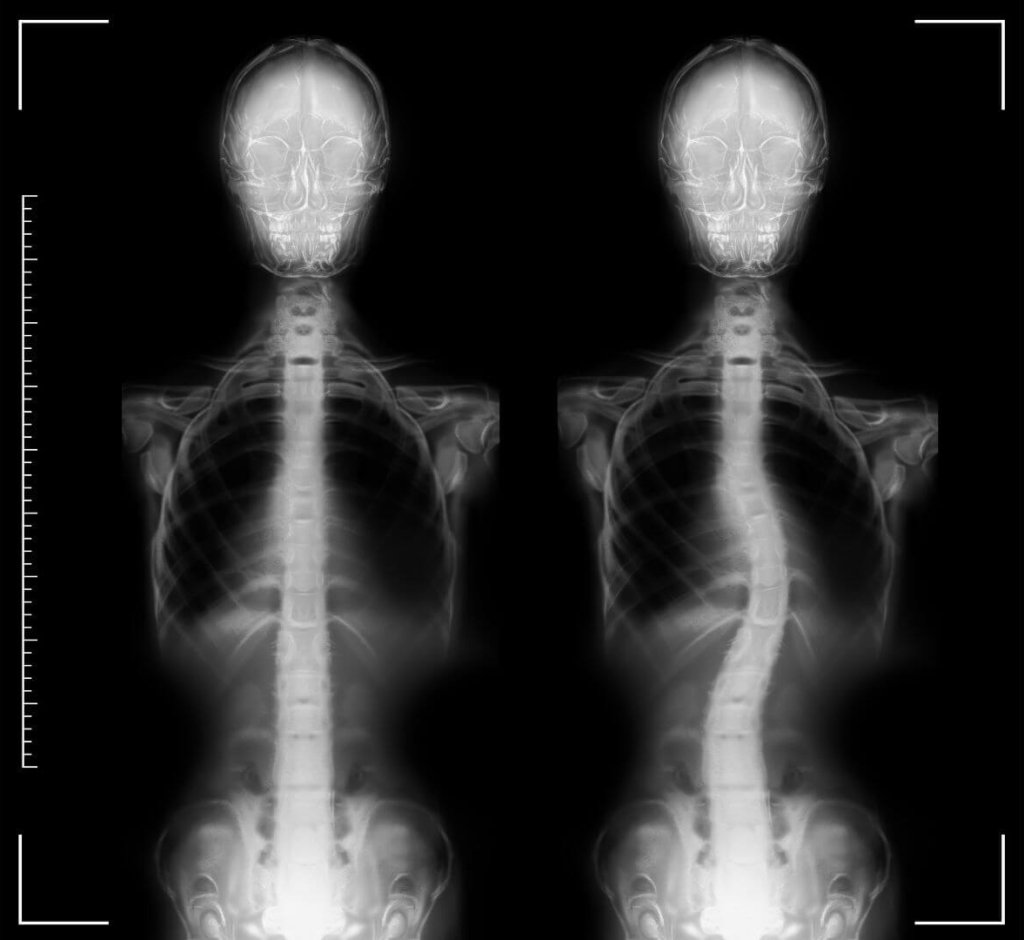

La scoliosi è una condizione complessa della colonna vertebrale, caratterizzata da una deviazione laterale accompagnata dalla rotazione dei corpi vertebrali.

Questa deformità può interessare l’intero rachide della colonna o solo porzioni specifiche, a seconda della localizzazione della curvatura.

Per scoliosi si intende una curvatura anomala della colonna vertebrale, generalmente superiore ai 10° di Cobb, che rappresenta il valore di riferimento per la diagnosi.

La scoliosi non è, come spesso si pensa, causata da posture errate o comportamenti quotidiani sbagliati, ma è il risultato di una deformità strutturale dei corpi vertebrali, i quali ruotano lateralmente. Questa condizione è, quindi, più correttamente definita “rotoscoliosi”.

La scoliosi si presenta tipicamente con una curvatura laterale della colonna vertebrale, che può associarsi a:

- Gibbo costale: un rialzo della zona toracica che si forma a causa della rotazione delle vertebre.

- Asimmetria delle spalle e dei fianchi: in molti casi, uno dei fianchi o delle spalle appare più alto rispetto all’altro.

A seconda della gravità e della localizzazione della curvatura la scoliosi può essere classificata come lombare, dorsale, dorso-lombare o cervico-dorsale.